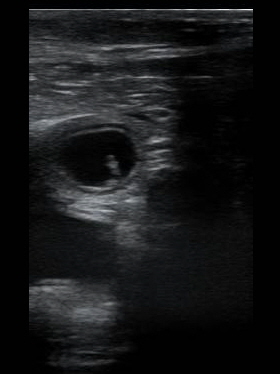

So 02. 11. 2025 - Mo 10. 11. 2025 Die Augen und die Nervenstränge im Rückenmark werden gebildet. Die Organbildung beginnt. In dem derzeitigen Zustand sind die Embryonen sehr stark defektgefährdet. Die Entwicklung der Zitzen beginnt. Mittwoch, den 05. 11. 2025 Heute waren wir mit Daica bei der Tierärztin, die Ultraschalluntersuchung stand an. Ich war mir eigentlich s chon seit mehr als einer Woche sicher, daß “es“ geklappt hat, Daica ist im Wesen etwas verändert. Sie ist sehr verschmust und ich konnte bereits kleine körperliche Veränderungen feststellen. Wir haben bei der Untersuchung 5, 6 Früchte erkennen können und gehen jetzt, wenn alles glatt läuft, von einem starken Wurf Mitte Dezember aus. Der Daica geht`s gut. Sie ist fit.